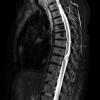

NEOPLASMS (MENINGIOMA)

Transitional (4)